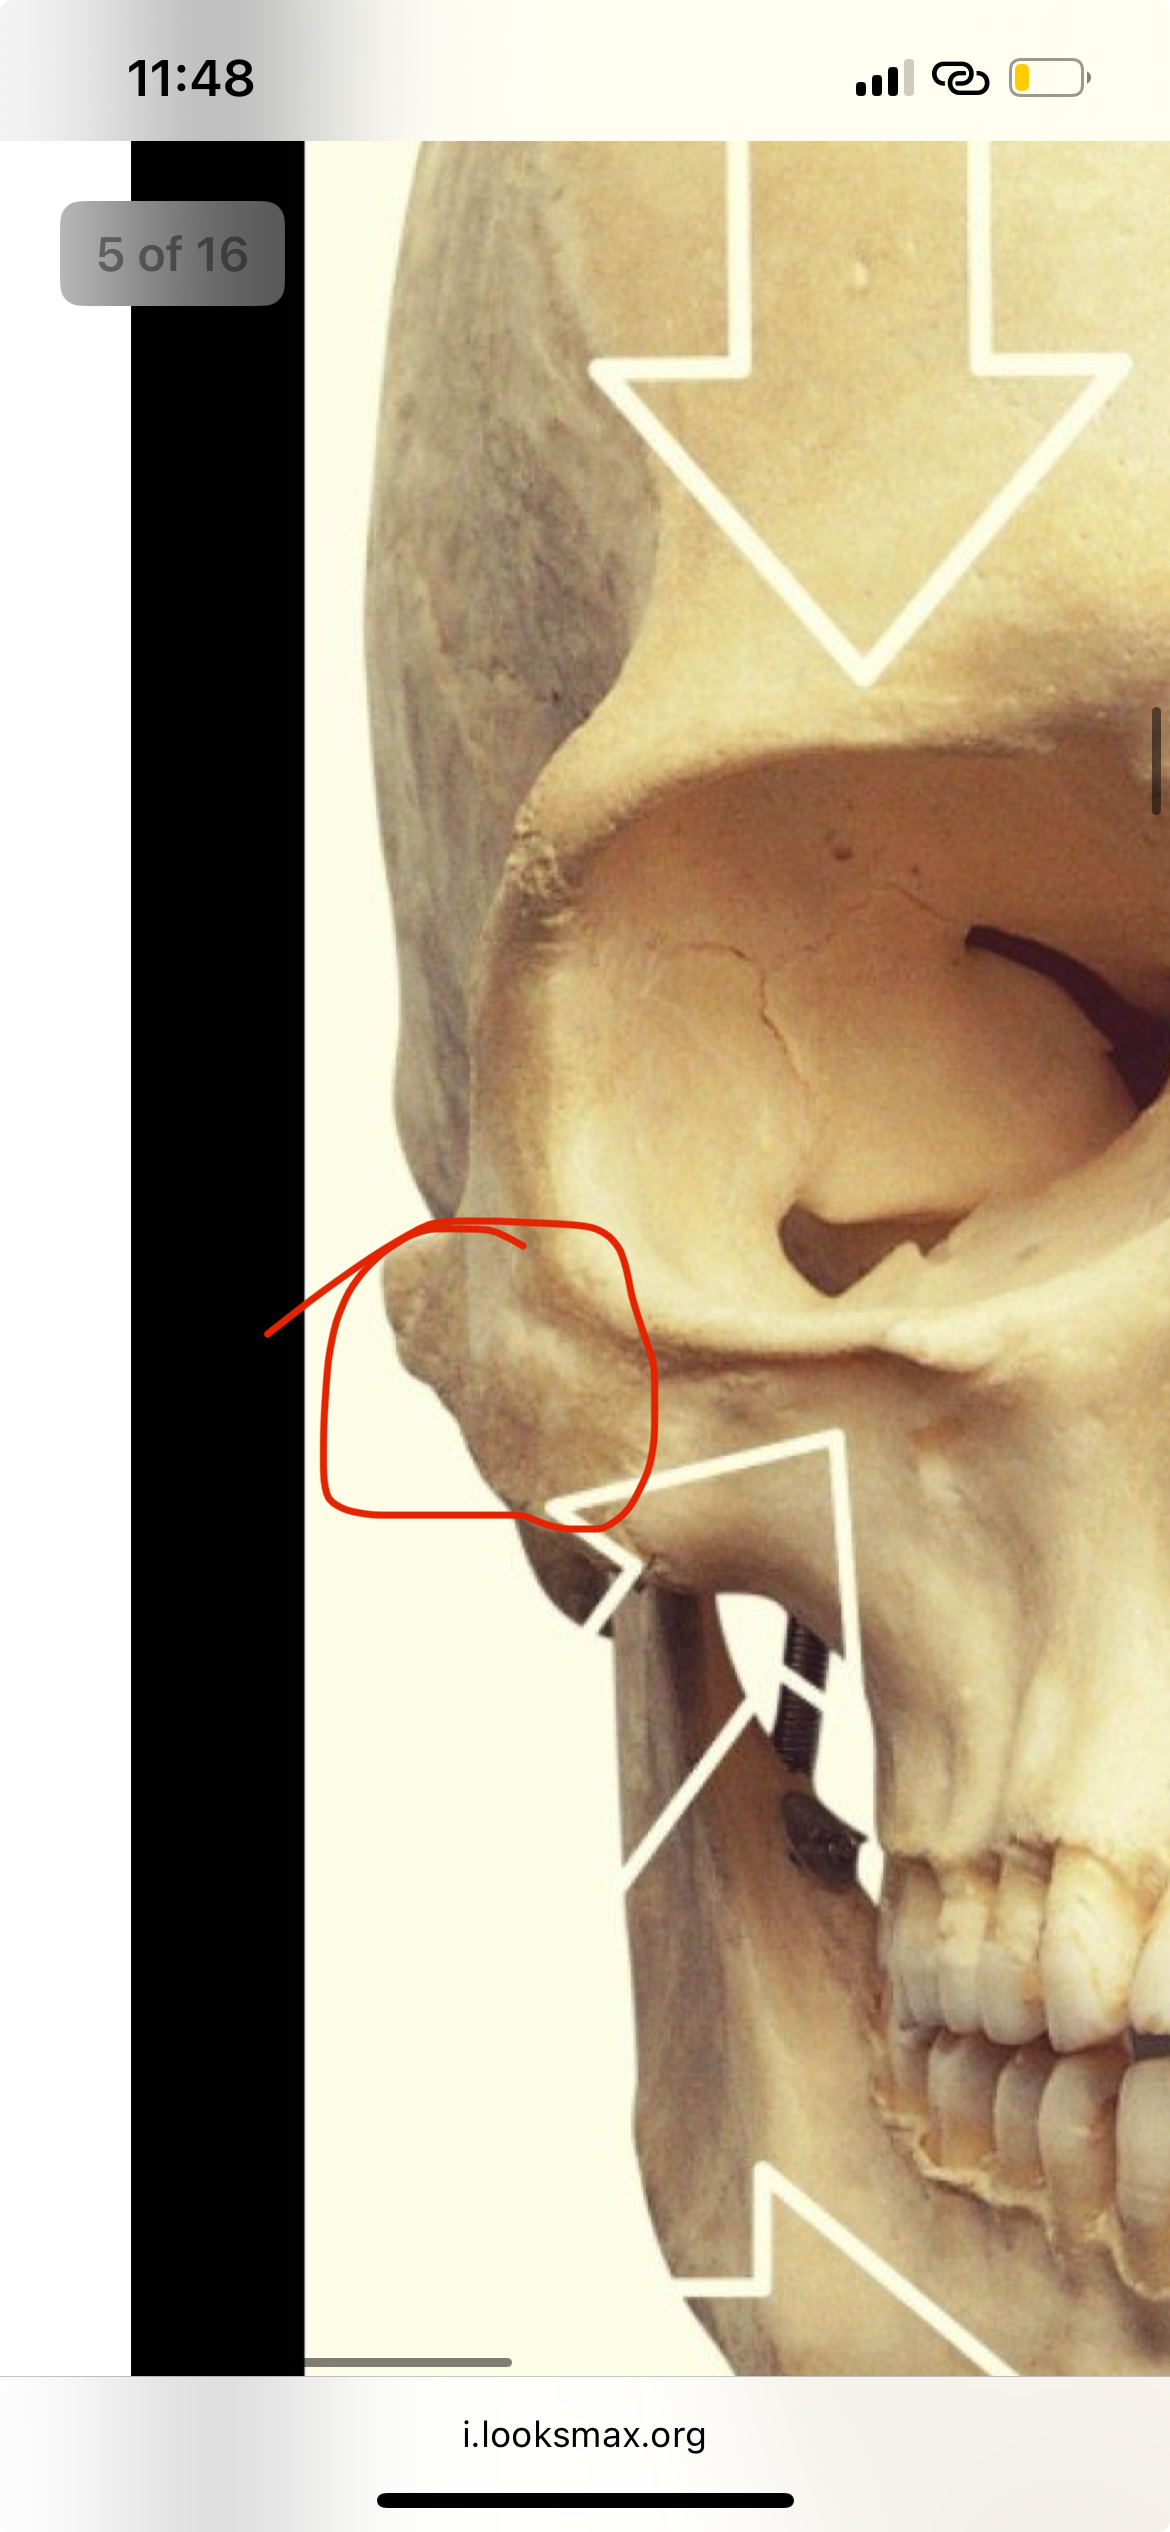

im hitting the sides of my zygos and my chin wait lemme send a picWhere are u hitting and how much growth have u seen

@pfl @slatersim hitting the sides of my zygos and my chin wait lemme send a pic

How am i suppose to not hit a nerve on zygos bro

View attachment 4458013